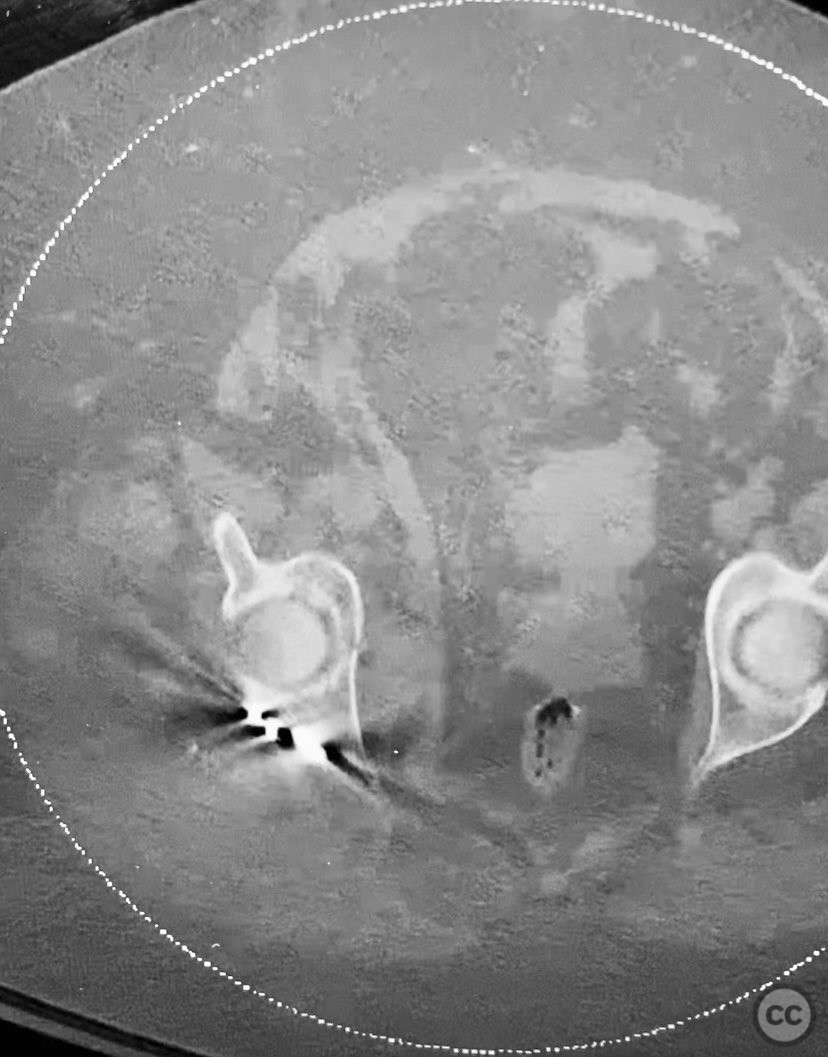

Clinical and radiological findings:  The patient is morbidly obese and sustained an unstable, displaced posterior column/posterior wall (PC/PW) acetabular fracture. Axial computed tomography images revealed a 2x2x1.5 cm pyramidal chondrocancellous articular fragment wedged in the fracture plane near the incisura ischiadica major (greater sciatic notch). Surface-rendered reconstructions further delineated the fracture morphology and fragment position. Obesity was noted to complicate all aspects of management, including anatomical localization, intraoperative imaging, and soft tissue handling.

Planning remarks:  The preoperative plan involved open reduction and internal fixation of the posterior column and posterior wall fragments, with retrieval and anatomic reduction of the intra-articular chondrocancellous fragment. A Kocher-Langenbeck approach was selected for direct access to the posterior acetabulum. Contoured plates and screws were prepared for definitive fixation.

Orthopaedic implants used:   Contoured reconstruction plates; cortical screws